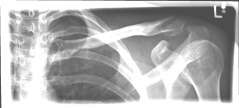

Pictures: Here, an angle-stable plate was used to supply the clavicle fracture near the shoulder joint. This plate makes it possible to anchor many screws in the fragment and thus obtain a good stabilization.